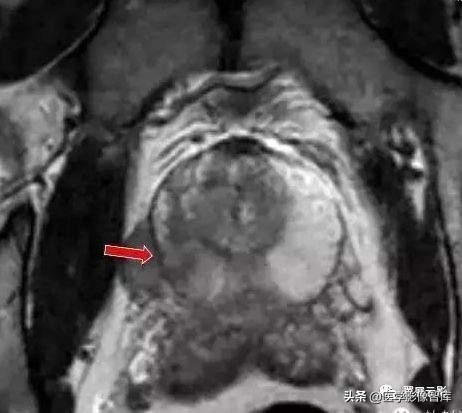

多囊肾

本病常合并多囊肝,此为先天性常染色体显性遗传性疾病,多数学者认为多囊肝是在多囊肾的基础上基因突变的结果,并定位于16号染色体上,也有学者认为该病是由于胚胎发育不良所导致,于胚胎早期管道形成时排列失常,造成无数迷管,于胚胎晚期未退化,且逐渐扩张成囊,成多发性囊肿病,根据发病年龄的不同,将其分为儿童型和成人型,本病多发生于双侧肾脏,可继发感染,结石以及囊内出血和囊壁钙化,也可以恶变,并有阻塞性黄疸及合并皮下囊肿的报道,临床上早期无症状,就诊时肾脏功能已经不同程度受损,肝功能受损程度较轻。

MRI表现为双肾增大和分叶状轮廓,多发囊肿多数为长T1长T2信号,出血性囊肿可为短T1长T2信号或长T1短T2信号,增强扫描所有病灶均不强化,应同时观察合并的多囊肝及胰脾多发囊肿。